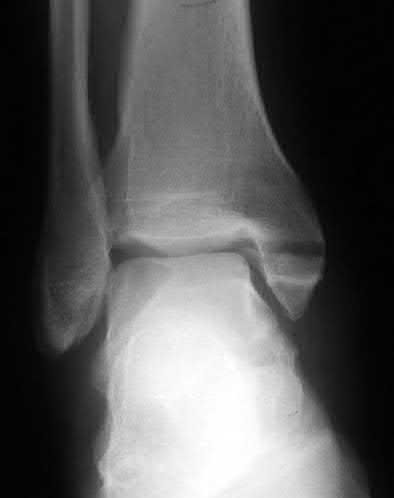

A 28-year-old male sustains a severe hyper-dorsiflexion injury to his ankle in a motor vehicle accident, resulting in a Hawkins Type III talar neck fracture. Which of the following arteries provides the predominant blood supply to the body of the talus, placing it at significant risk for avascular necrosis in this injury?

The artery of the tarsal canal, which is a branch of the posterior tibial artery, provides the dominant blood supply to the talar body. In a Hawkins Type III fracture (talar neck fracture with subtalar and tibiotalar dislocation), the blood supply from the artery of the tarsal canal, the artery of the sinus tarsi, and capsular vessels are disrupted, leading to an avascular necrosis (AVN) rate approaching 100%.